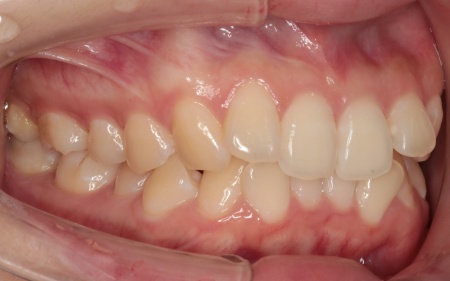

歯並びがある程度正しい位置に並んだら、マウスピース矯正で微調整を行いました。

歯の移動が完了したあとは定期的に経過を確認しながら、後戻りを防ぐためのリテーナー(保定装置)を継続して使用いただき、治療を終了しました。